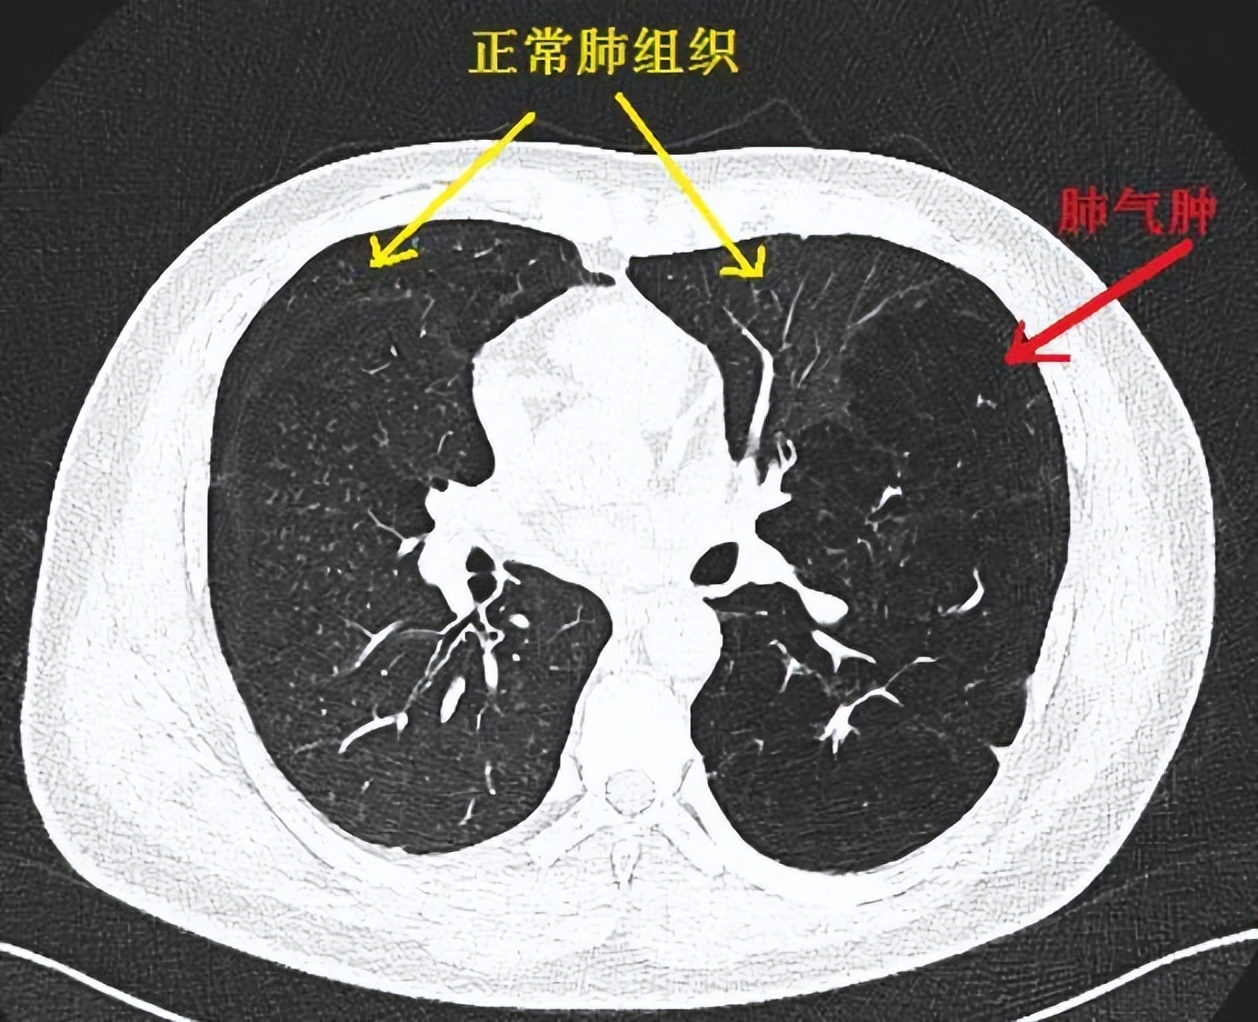

众所周知,肺部对于人体来说是一个尤为重要的器官,它掌管着我们的呼吸功能,通过不断吸入和排出气体,实现机体与外界环境之间的气体交换,维持人体生命活动。因此,一旦患上类似肺气肿这类严重的疾病,对肺功能影响是很大的。

肺是机体气体交换的场所,由于某些病因导致肺充气过度、气道弹性减退、过度膨胀、充气和肺容积增大或同时伴有气道壁破坏,以致肺功能减退而引起的一种阻塞性肺疾患,常继发于慢性支气管炎,支气管哮喘和肺纤维化。